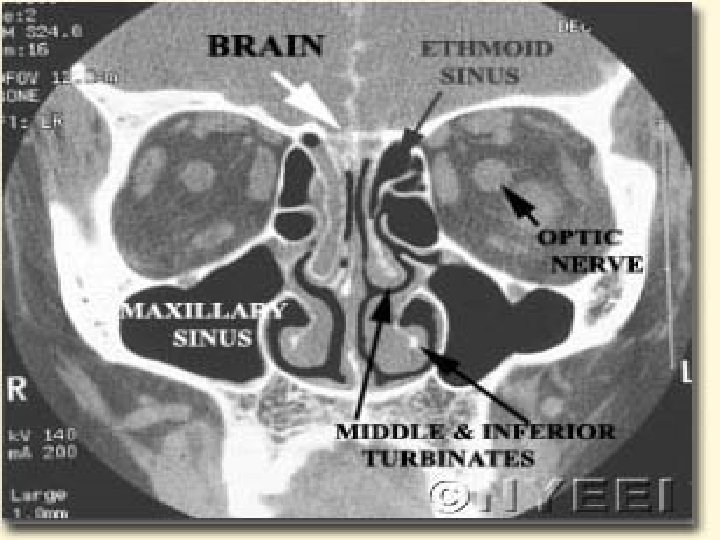

Localization of the leak Radiology plays the key role to see the anatomical site, size, side of the fistula n Bone defects, air fluid levels and erosions can be seen. n Plain X rays… Pneumocephalus/ air fluid levels n CT scan in axial/ coronal views… Skull Base #s, CSF fistulae n MRI… is not used as it is unable to show bone windows n